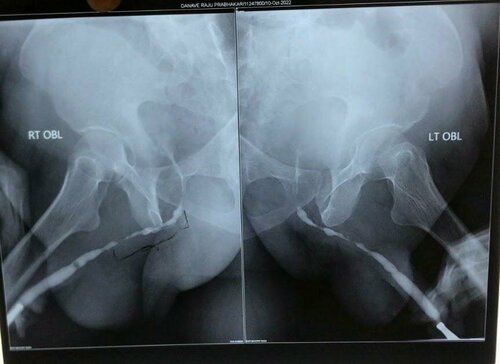

A 58 years old male was having difficulty in passing urine. He had underwent multiple endoscopic operation for stricture in urinary pipe in past. RGU ...